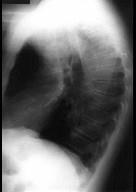

问题 男性,53岁,2年前被踢伤胸部,最近感胸部不适,常规胸片检查,示纵隔内病变,加扫CT平扫及增强,结果如图所示 ( )

选项 A、球形病灶外围见半月形低密度影,其内有斑片状高密度影,考虑为血栓形成 B、结合临床,考虑为主动脉假性动脉瘤(外伤性) C、CT增强扫描示主动脉弓层面左侧缘不规则,造影剂流入球形病灶内 D、结合临床,考虑为主动脉夹层 E、胸片示上纵隔见类圆形高密度影,以侧位片明显

答案 ABCE